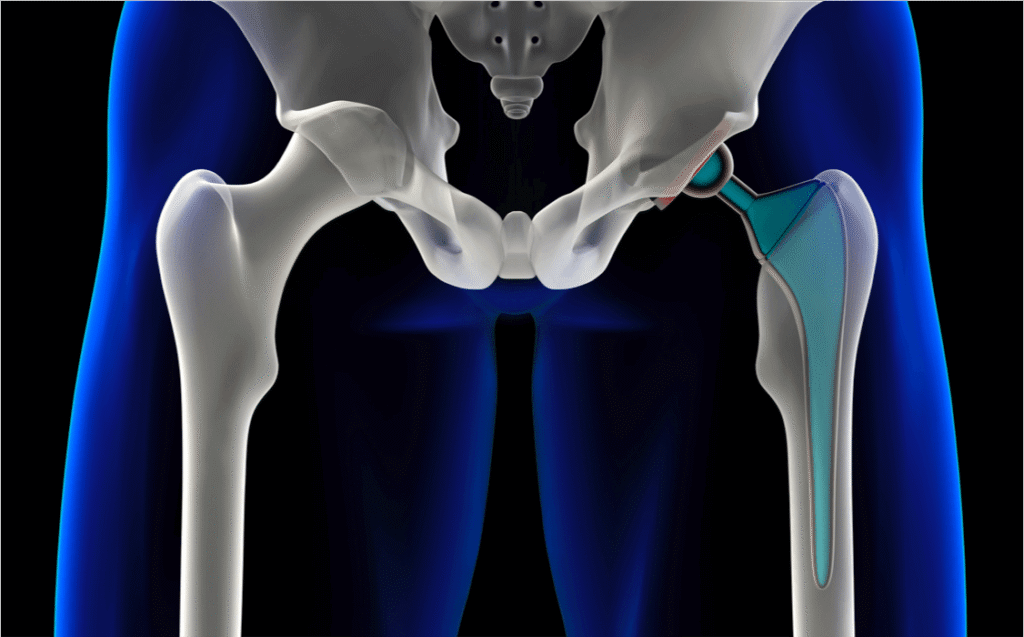

Kalça protezi, hasarlı bir kalça ekleminin (protez olarak bilinen) yapay bir protezle değiştirildiği yaygın bir ameliyat türüdür. Her yaştaki yetişkinler kalça protezi için düşünülebilir, ancak çoğu 60 ila 80 yaş arasındaki kişilerde gerçekleştirilir. Modern bir yapay kalça eklemi en az 15 yıl dayanacak şekilde tasarlanmıştır. Çoğu insan ağrıda belirgin bir azalma ve hareket aralığında bir miktar iyileşme yaşar. Kalça protezi ameliyatının en sık sebebi osteoartrittir. Kalça eklemi hasarına neden olabilecek diğer durumlar şunlardır: Romatoid artrit Kalça kırığı Septik artrit Ankilozan spondilit Olağandışı kemik büyümesine neden olan bozukluklar (kemik displazileri)